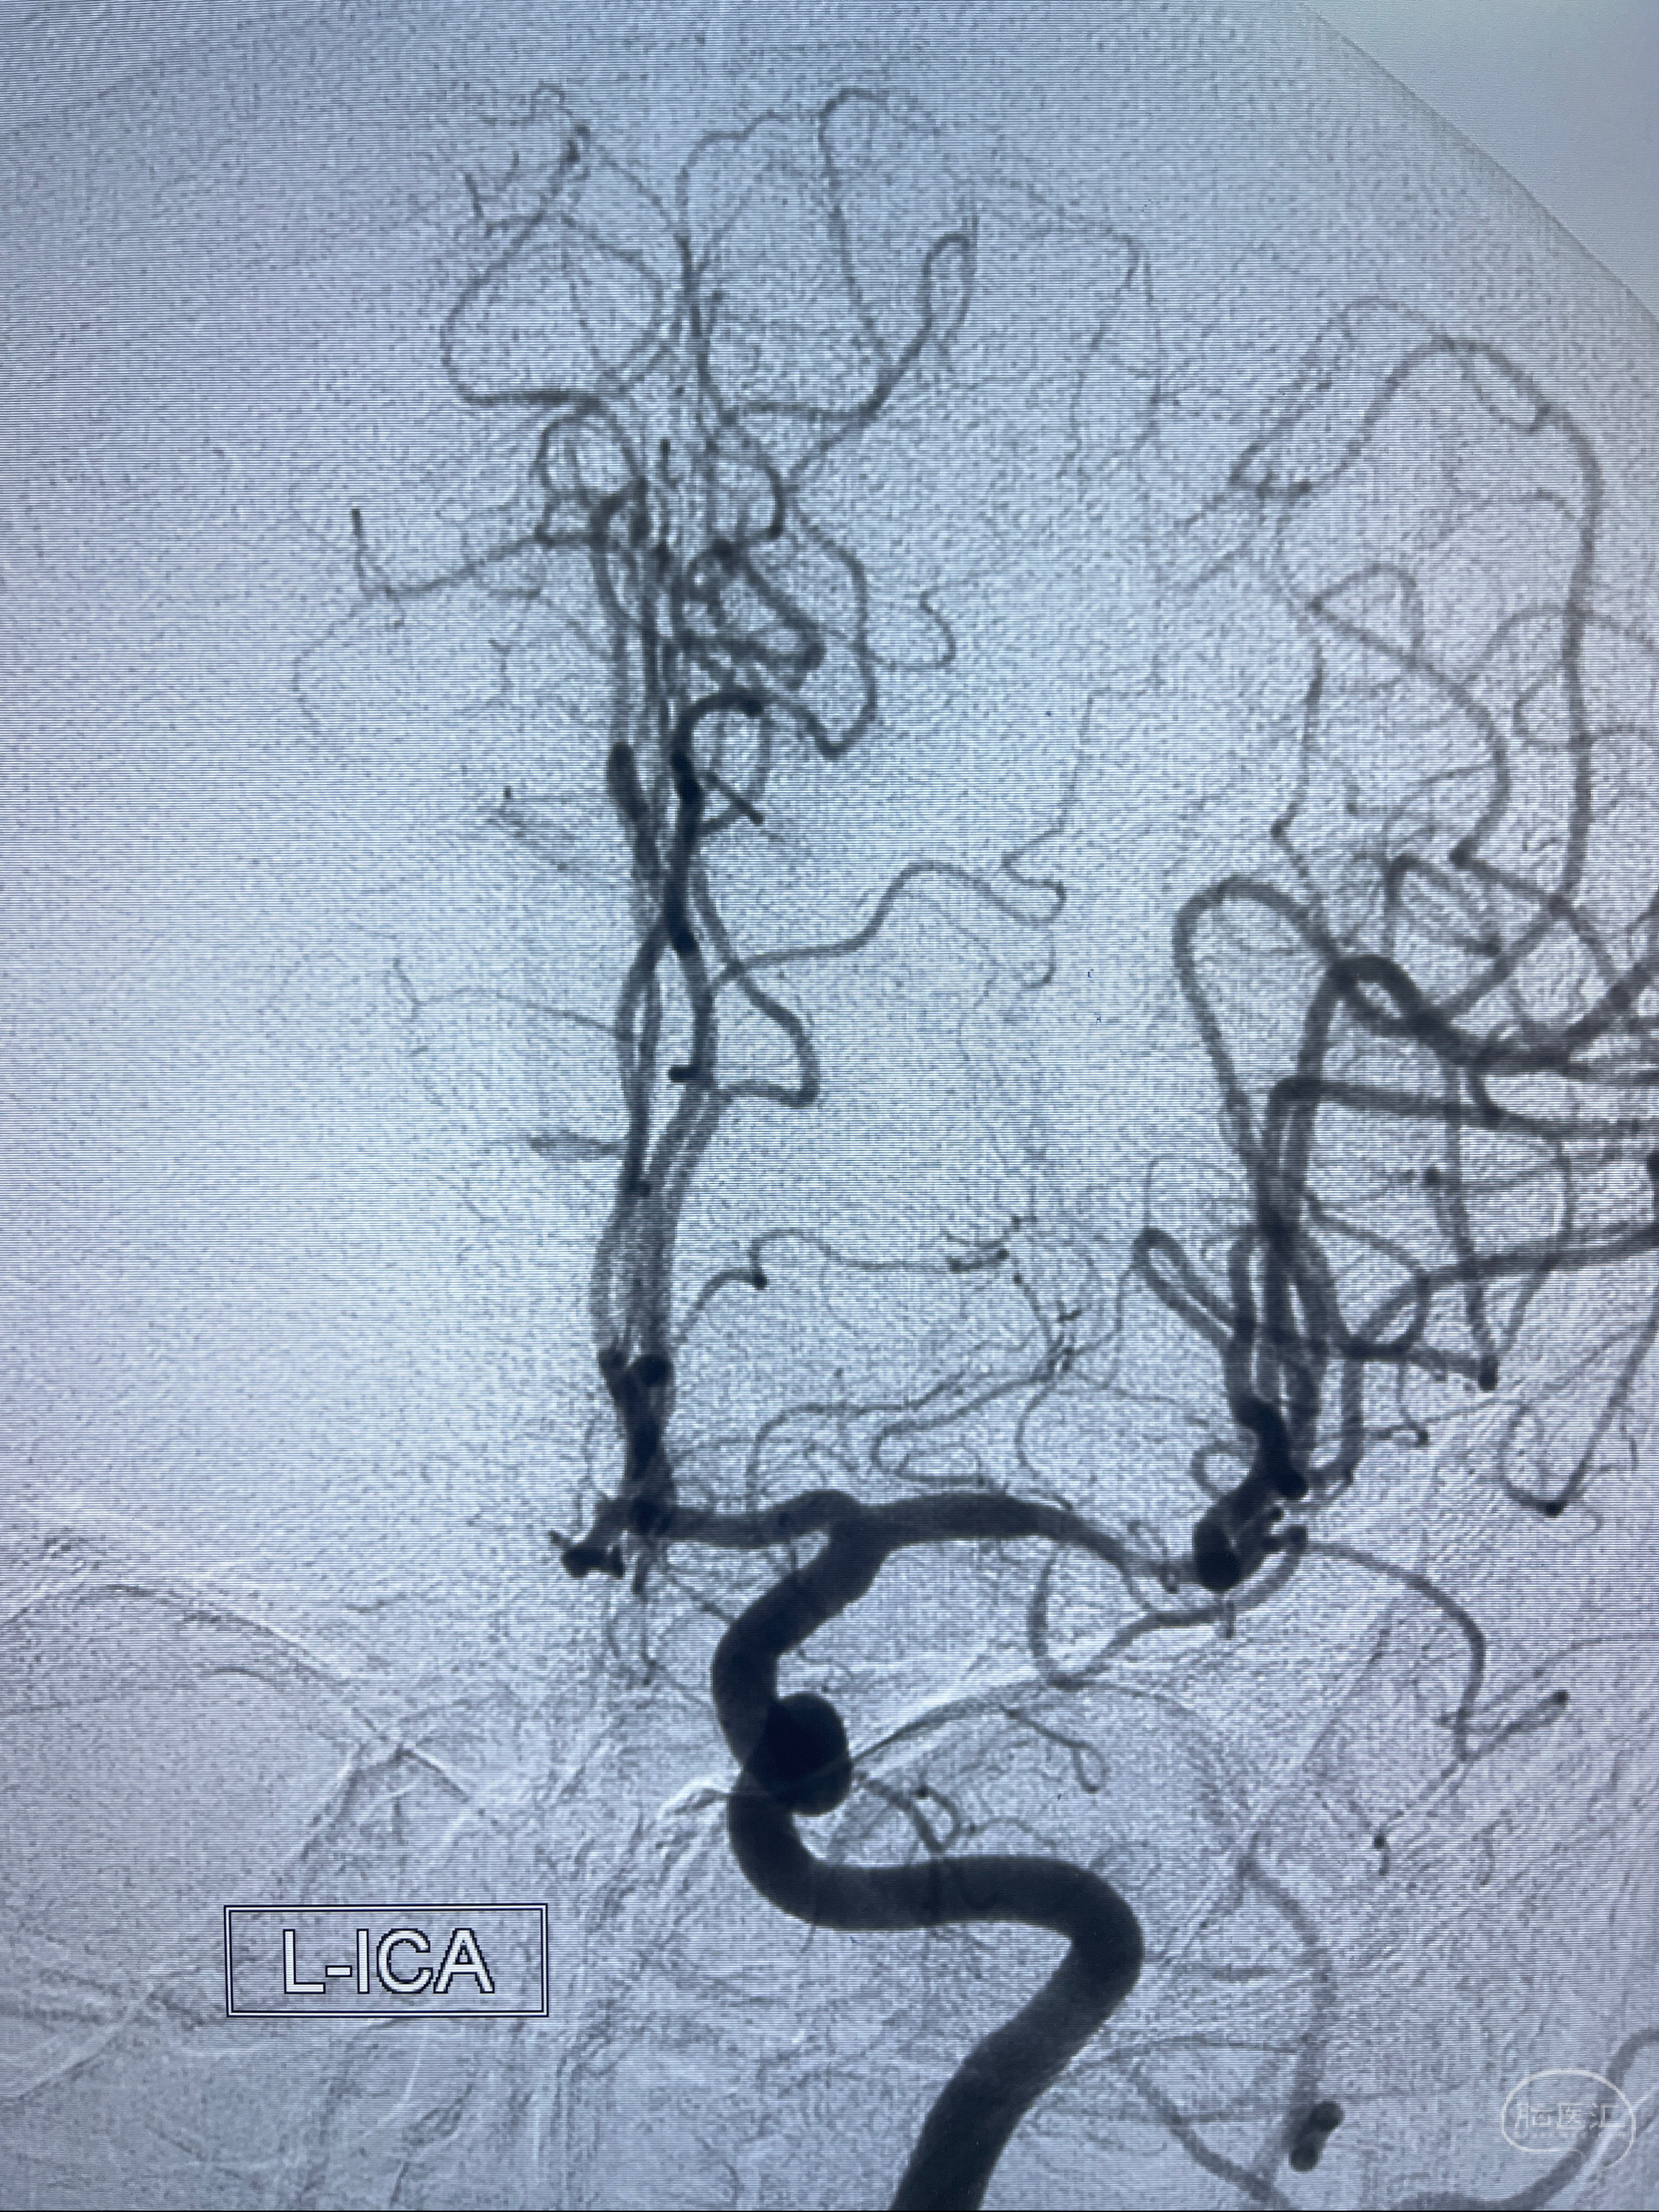

2023-02-02 沛县人民医院 头颅CTA:大脑动脉环发育变异,头颈部动脉粥样硬化,双侧颈内动脉及椎动脉颅内段多发狭窄;

2023-02-15DSA